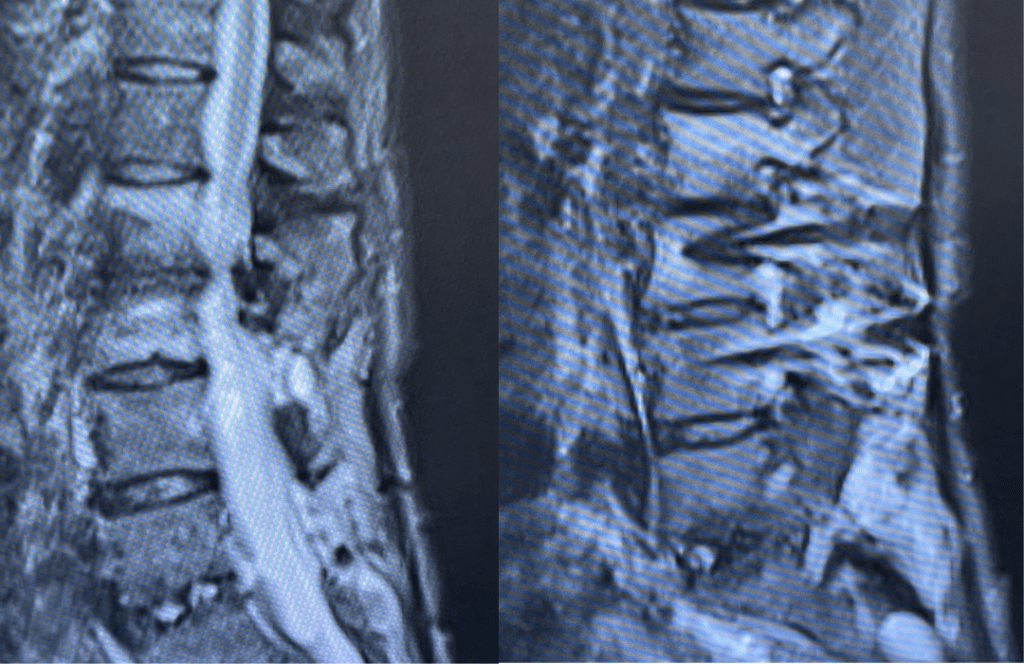

Figures 1a and 1b. Sagittal T2 MRIs of the lumbar spine demonstrating L2-3 stenosis after L3-4 instrumented fusion.

Figure 2. Axial T2 MRI of the lumbar spine demonstrating L2-3 stenosis due to significant facet arthropathy.